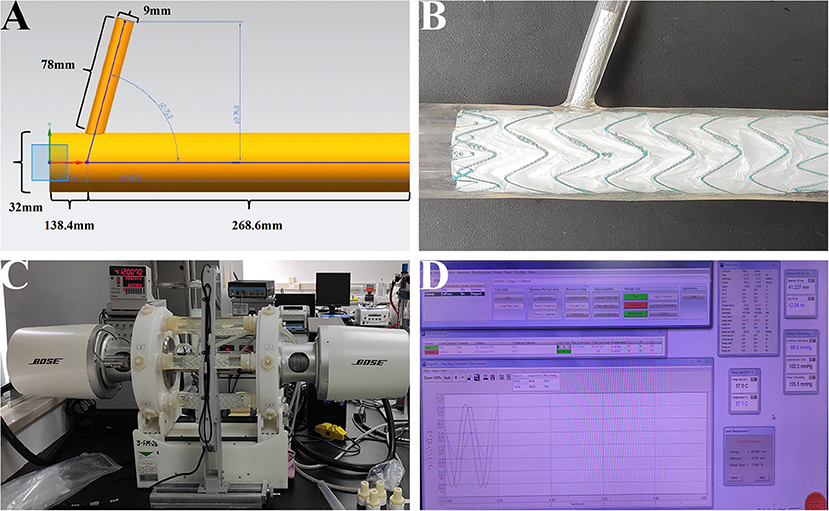

The purpose of this study was to examine whether there was disconnection, fabric breakage, or metal structure fracture on main/branch stent grafts after a fatigue test. When the stent grafts were engaged in silicone models (Figures 2A,B), the models were then installed into the fatigue test machine (Figure 2C, Bose Testing System, Minnetonka, USA). The parameters were automatically controlled by the computer (Figure 2D, WinTest Automatic Test Equipment, Yokohama, Kanagawa Prefecture, Japan), in which the average systolic/diastolic water pressure was 130/80 mm Hg and the beating rate maintained at 1,000 bpm. The solution utilized in the experiment was non-ionized water at 37°C (9). The total machine running time was 183 days to stimulate the total number of 5-year heartbeats with 100 bpm (262,800,000 cardiac cycles in all).

Figure 2. In-vitro fatigue experiment on the MCPF stent grafts in silicone models. (A) The diagram of the silicone model. (B) The main and branch stent grafts were implanted into the silicone model. (C) After stent grafts implantation, all the silicone models were installed into the fatigue test machine to stimulate the relative movement of the aorta and branch artery with the aortic pulsation. (D) The parameters were automatically controlled by the computer, in which the temperature was 37°C, the average systolic/diastolic water pressure was 130/80 mm Hg, and the beating rate was 1,000 bpm. MCPF, mini-cross prefenestration.